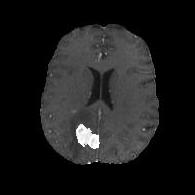

We argue that the sub-optimal paradigm of processing different abstractions within a single CNN pipeline can be remedied through the effective processing of information in a structured manner. Consequently, we devise strategies for disentangling the edge and texture information within a single training pipeline. Figure 2 illustrates how our proposed module, dubbed EG-CNN, can be paired with any existing CNN encoder-decoder to improve segmentation quality near intensity edges. We have applied our EG-CNN to the tasks of brain and liver tumor segmentation in medical images (Figure 3).

(1) Brain MR (2) Liver MR (3) Liver CT (4) Lung CT